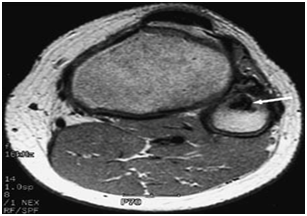

The classic plain radiographic findings of PVNS consist of cystic erosions, increased density of the synovium, secondary to hemosiderin deposition and peri-articular soft-tissue swelling with no calcification.8 Magnetic resonance imaging usually demonstrates key diagnostic features, which include joint effusion, elevation of the joint capsule, hyperplastic synovium and low signal intensity resulting from hemosiderin deposition.2 In patients with diffuse pigmented villonodular synovitis of the knee, magnetic resonance imaging (MRI) may show a large effusion, low signal intensity on both T1 and T2 weighted images (because of hemosiderin deposition), hyperplastic synovium and occasional bony erosions (Figure 1) and (Figure 2).

Figure 2 T2-weighted MRI scan showing a lesion in the proximal fibula (arrow) that has a low intensity consistent with pigmented villonodular synovitis.